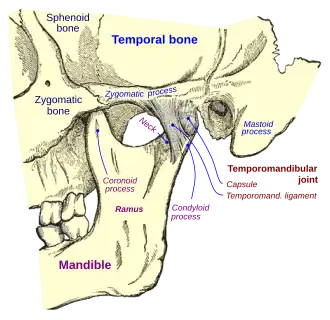

Temporomandibular joints

The temporomandibular joints are the dual articulation of the mandible with the skull. Each TMJ is classed as a "ginglymoarthrodial" joint since it is both a ginglymus (hinging joint) and an arthrodial (sliding) joint,[36] and involves the condylar process of the mandible below, and the articular fossa (or glenoid fossa) of the temporal bone above. Between these articular surfaces is the articular disc (or meniscus), which is a biconcave, transversely oval disc composed of dense fibrous connective tissue. Each TMJ is covered by a fibrous capsule. There are tight fibers connecting the mandible to the disc, and loose fibers which connect the disc to the temporal bone, meaning there are in effect 2 joint capsules, creating an upper joint space and a lower joint space, with the articular disc in between. The synovial membrane of the TMJ lines the inside of the fibrous capsule apart from the articular surfaces and the disc. This membrane secretes synovial fluid, which is both a lubricant to fill the joint spaces, and a means to convey nutrients to the tissues inside the joint. Behind the disc is loose vascular tissue termed the "bilaminar region" which serves as a posterior attachment for the disc and also fills with blood to fill the space created when the head of the condyle translates down the articular eminence.[37] Due to its concave shape, sometimes the articular disc is described as having an anterior band, intermediate zone and a posterior band.[38] When the mouth is opened, the initial movement of the mandibular condyle is rotational, and this involves mainly the lower joint space, and when the mouth is opened further, the movement of the condyle is translational, involving mainly the upper joint space.[39] This translation movement is achieved by the condylar head sliding down the articular eminence, which constitutes the front border of the articular fossa.[28] The function of the articular eminence is to limit the forwards movement of the condyle.[28] The ligament directly associated with the TMJ is the temporomandibular ligament, also termed the lateral ligament, which really is a thickening of the lateral aspect of the fibrous capsule.[28] The stylomandibular ligament and the sphenomandibular ligament are not directly associated with the joint capsule. Together, these ligaments act to restrict the extreme movements of the joint.[40]